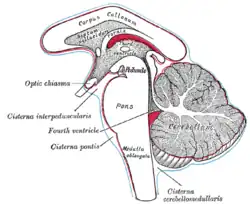

Base of brain. Diagram showing the positions of the three principal subarachnoid cisternæ.

Diagram showing the positions of the three principal subarachnoid cisternæ. Medulla oblongata